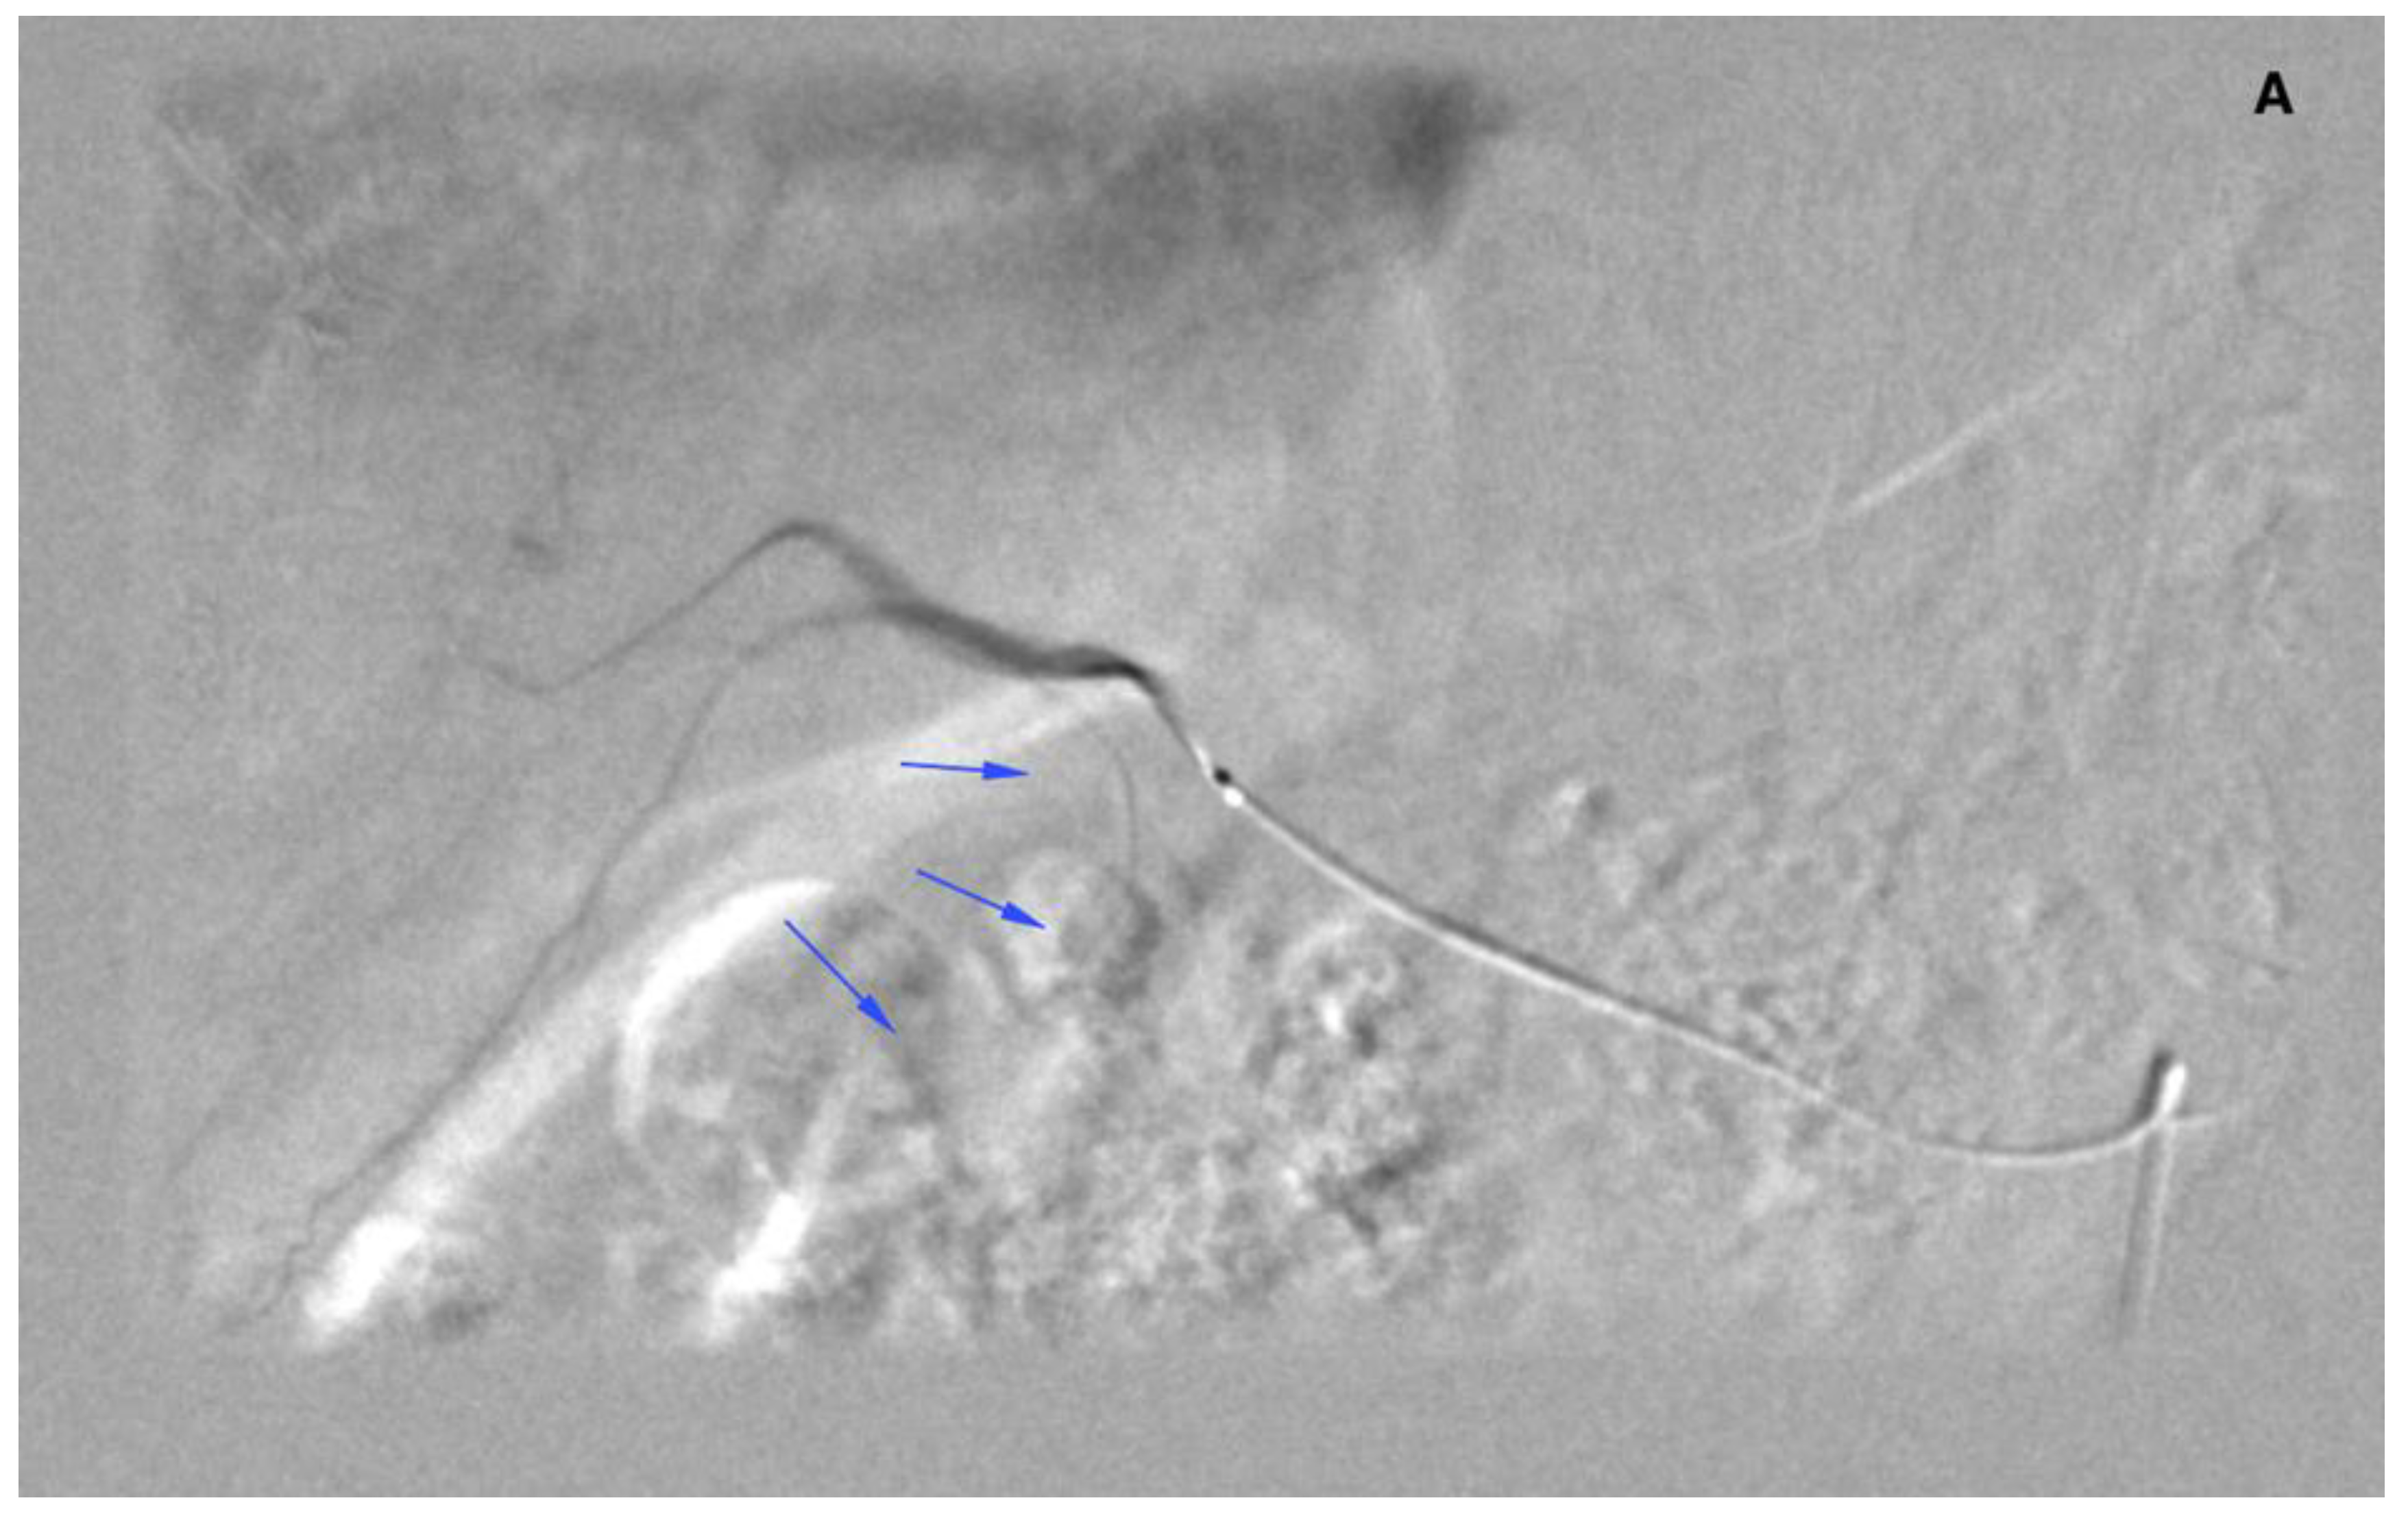

There were 20 patients after cholecystectomy. There were 30 (40%) patients with additional cystic arteries (Figure 3).

Figure 3.

Angiogram of the right hepatic artery. (A) Initially, single CA is visible (arrows) originating from the right hepatic artery division. (B) After embolization, another artery reveals multiple intrahepatic anastomoses to the gallbladder wall, and needs to be embolized. (C) There is insufficient embolization of both CA, and (D) retraction of the microcatheter reveals another CA originating proximally to the right hepatic artery division (arrows).

Mean distance of the right hepatic artery division from the cystic artery was 4.7 mm (0–35, 6 mm). The cystic artery originated from the right hepatic artery division in 14 patients.